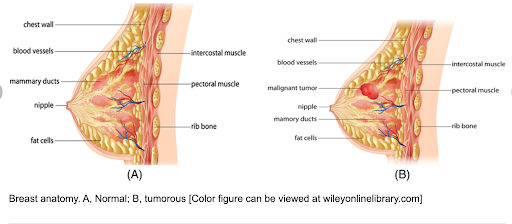

Which part of the body is involved?

Breast cancer usually begins in the breast tissue, particularly in the milk-producing glands (lobules) or the milk-carrying ducts. The breast also contains fatty tissue, connective tissue, blood vessels, and lymphatic vessels, which may be involved as the disease progresses.

Breast cancer usually begins in the breast tissue, particularly in the milk-producing glands (lobules) or the milk-carrying ducts. The breast also contains fatty tissue, connective tissue, blood vessels, and lymphatic vessels, which may be involved as the disease progresses.

Breast cancer develops when normal breast cells undergo changes affecting how they grow, divide, and die. Altered cells can multiply uncontrollably and may accumulate to form a mass. Over time, these cells may spread into nearby tissue or, in some cases, travel via lymphatic channels or blood vessels to other parts of the body.